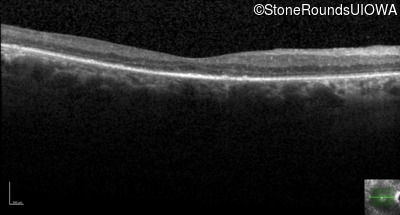

Age at visit: 59 years